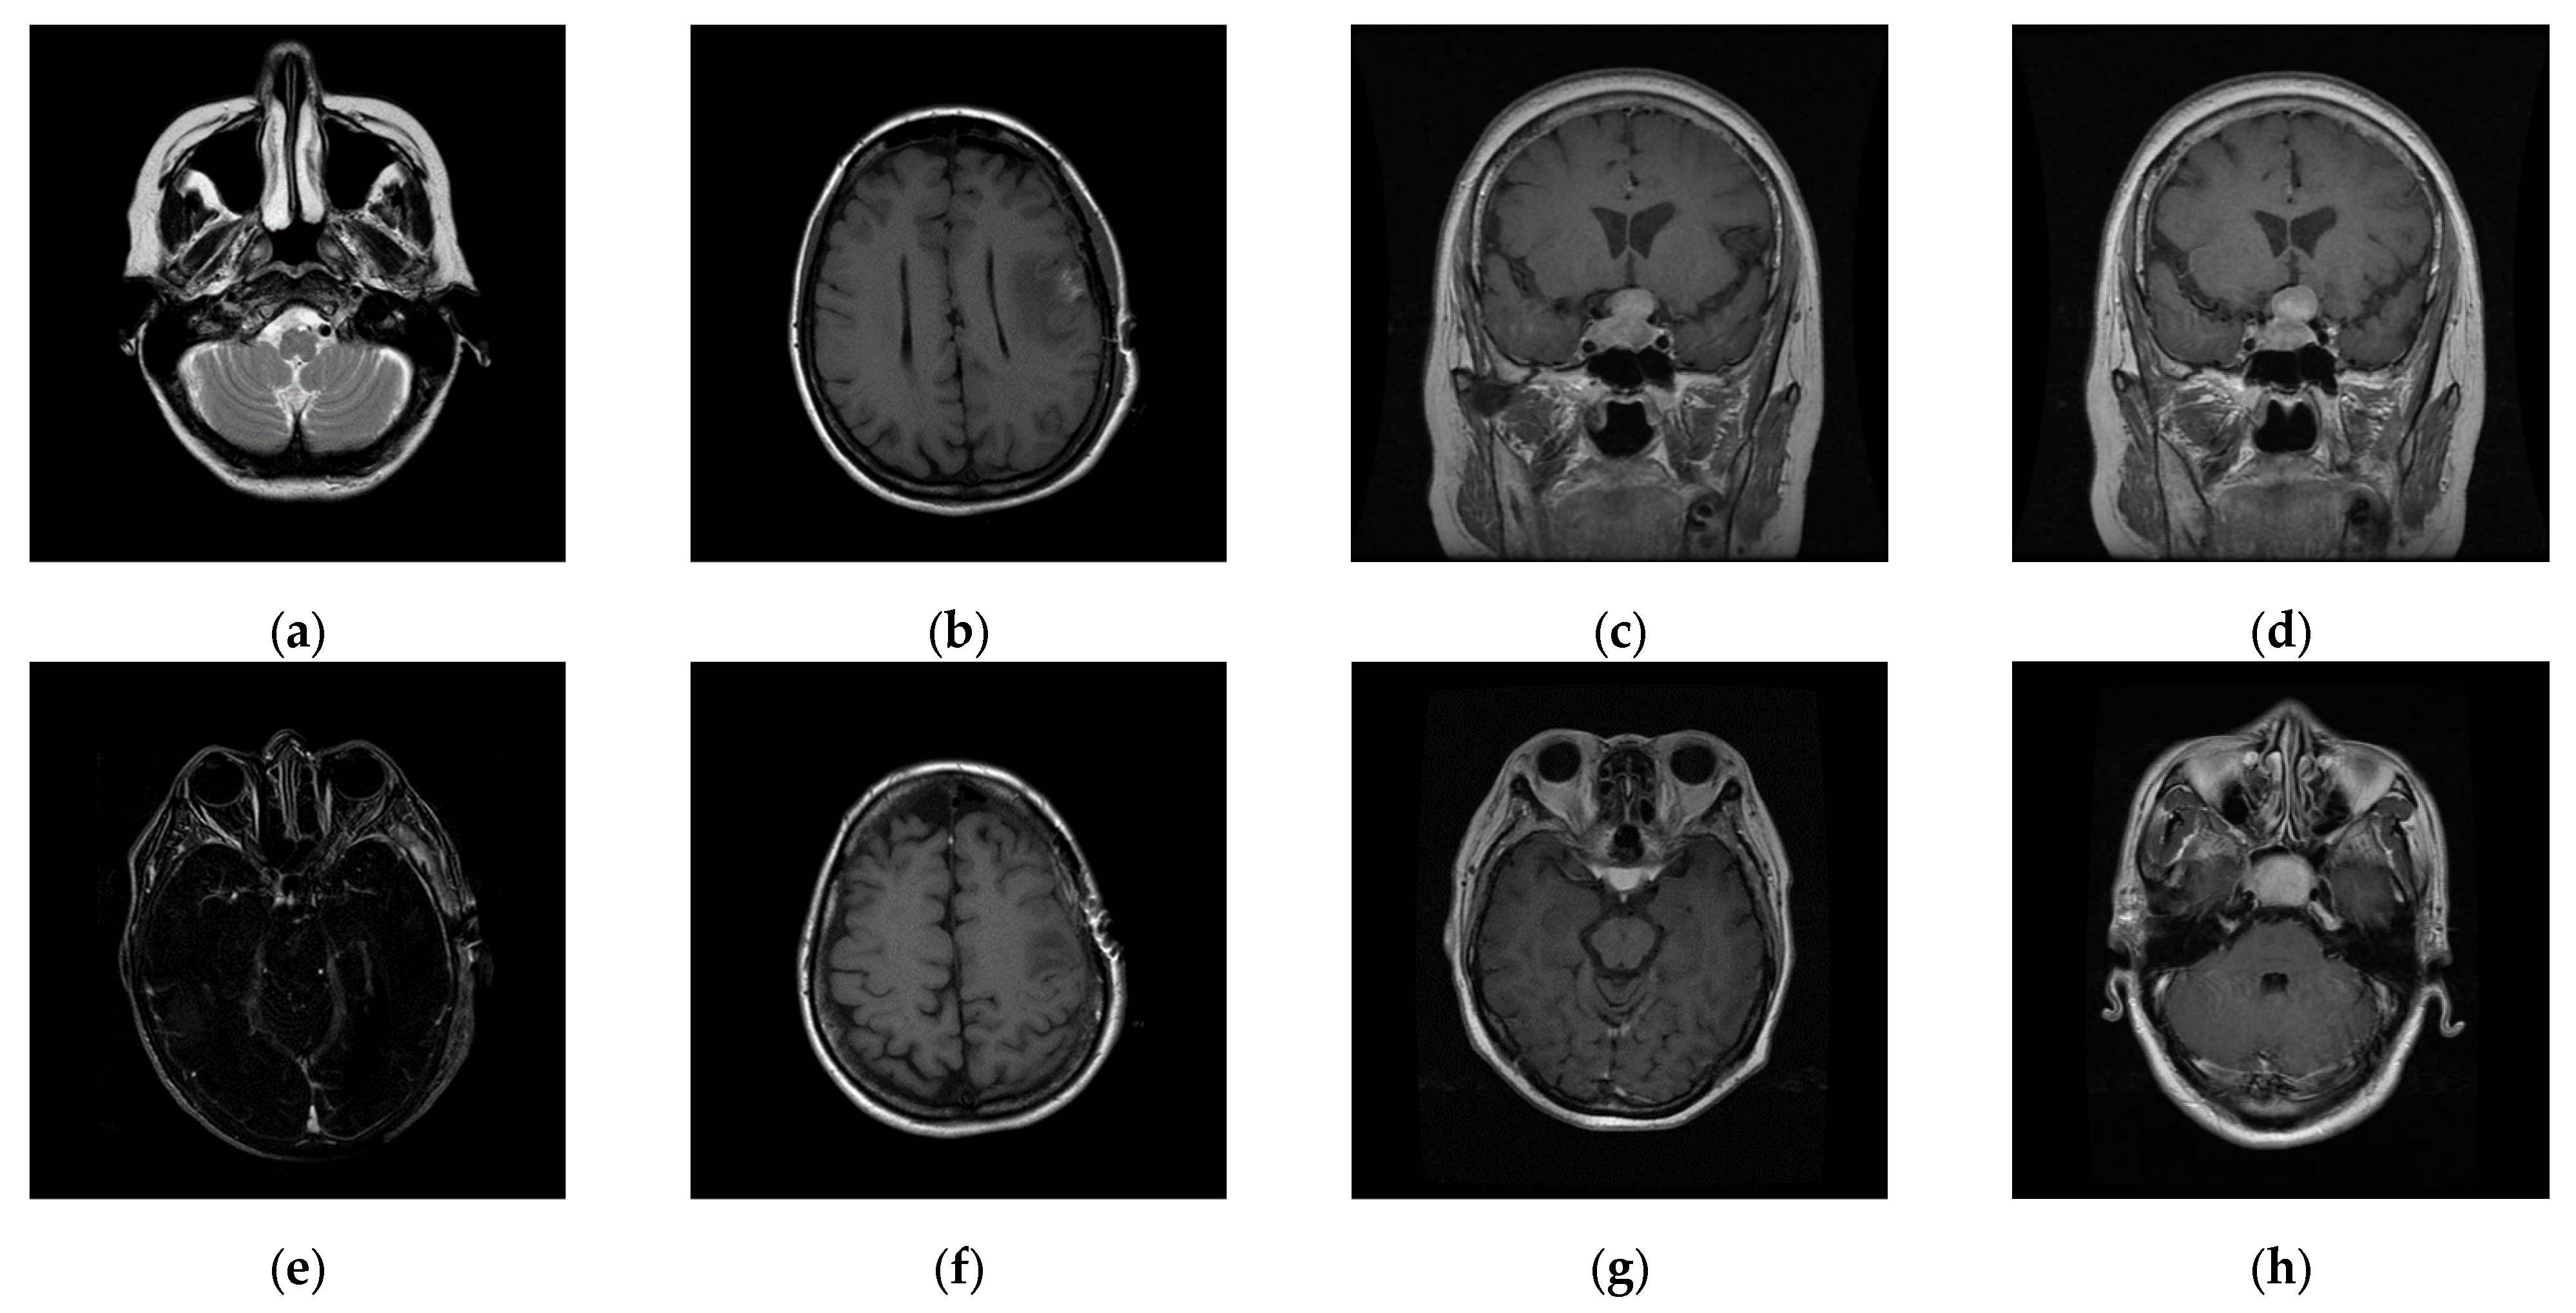

The experiments were conducted on two systems. The first system ran on Ubuntu 22.04, equipped with an Intel i7-9700KF CPU @ 3.60GHz (8 cores), an Nvidia GeForce RTX 3090 GPU, 32 GB of RAM, and Pytorch (https://pytorch.org/) for the experimentation. The second system, called the Type 1 device, is a notebook with an Intel(R) Core (TM) i7-10510U CPU @1.80 GHz 2.30 GHz, 16.0 GB RAM, 64-bit Windows operation system, and GPU MX 250. The third system, called the Type 2 device, is a notebook with an 11th Gen Intel(R) Core(TM) i5-11400H @ 2.70 GHz 2.69 GHz, 24.0 GB RAM, 64-bit Windows operation system, and GPU Nvidia GeForce 3060. The second system is a notebook that was released around 2019 or early 2020. The third system is also a notebook that was released in early 2021. The two systems were used to simulate resource-constrained environments. Different medical and test images were used as the test images to evaluate the performance of our proposed scheme and to make comparisons between our scheme and Qin et al.’s scheme [20]. In the first experiment, eight medical images, which are MRI scans of the brain, were randomly selected from the Osirix database [21] as test images and are presented in Figure 10 to demonstrate the performance of our proposed scheme in detail. In the second experiment, one hundred medical images, which are also MRI scans of the brain, were randomly selected from the Osirix database [21] to form Dataset 1 and Dataset 2, as shown in Figure 11, to prove the stable performance of our proposed scheme. In the third experiment, six general grayscale images, sized 512 × 512, demonstrated in Figure 12, were used to compare with those offered by Qin et al.’s scheme [20]. The logo depicted in Figure 13a was used as the watermark for the first and the second experiments and Figure 13b was used as the watermark for the third experiment.

Figure 11.

Two datasets are used to test the stable performance of the proposed scheme. (a–d) are Dataset 1, images of the pituitary gland taken from back to front. (e–h) are Dataset 2, images of the pituitary gland taken from top to bottom.